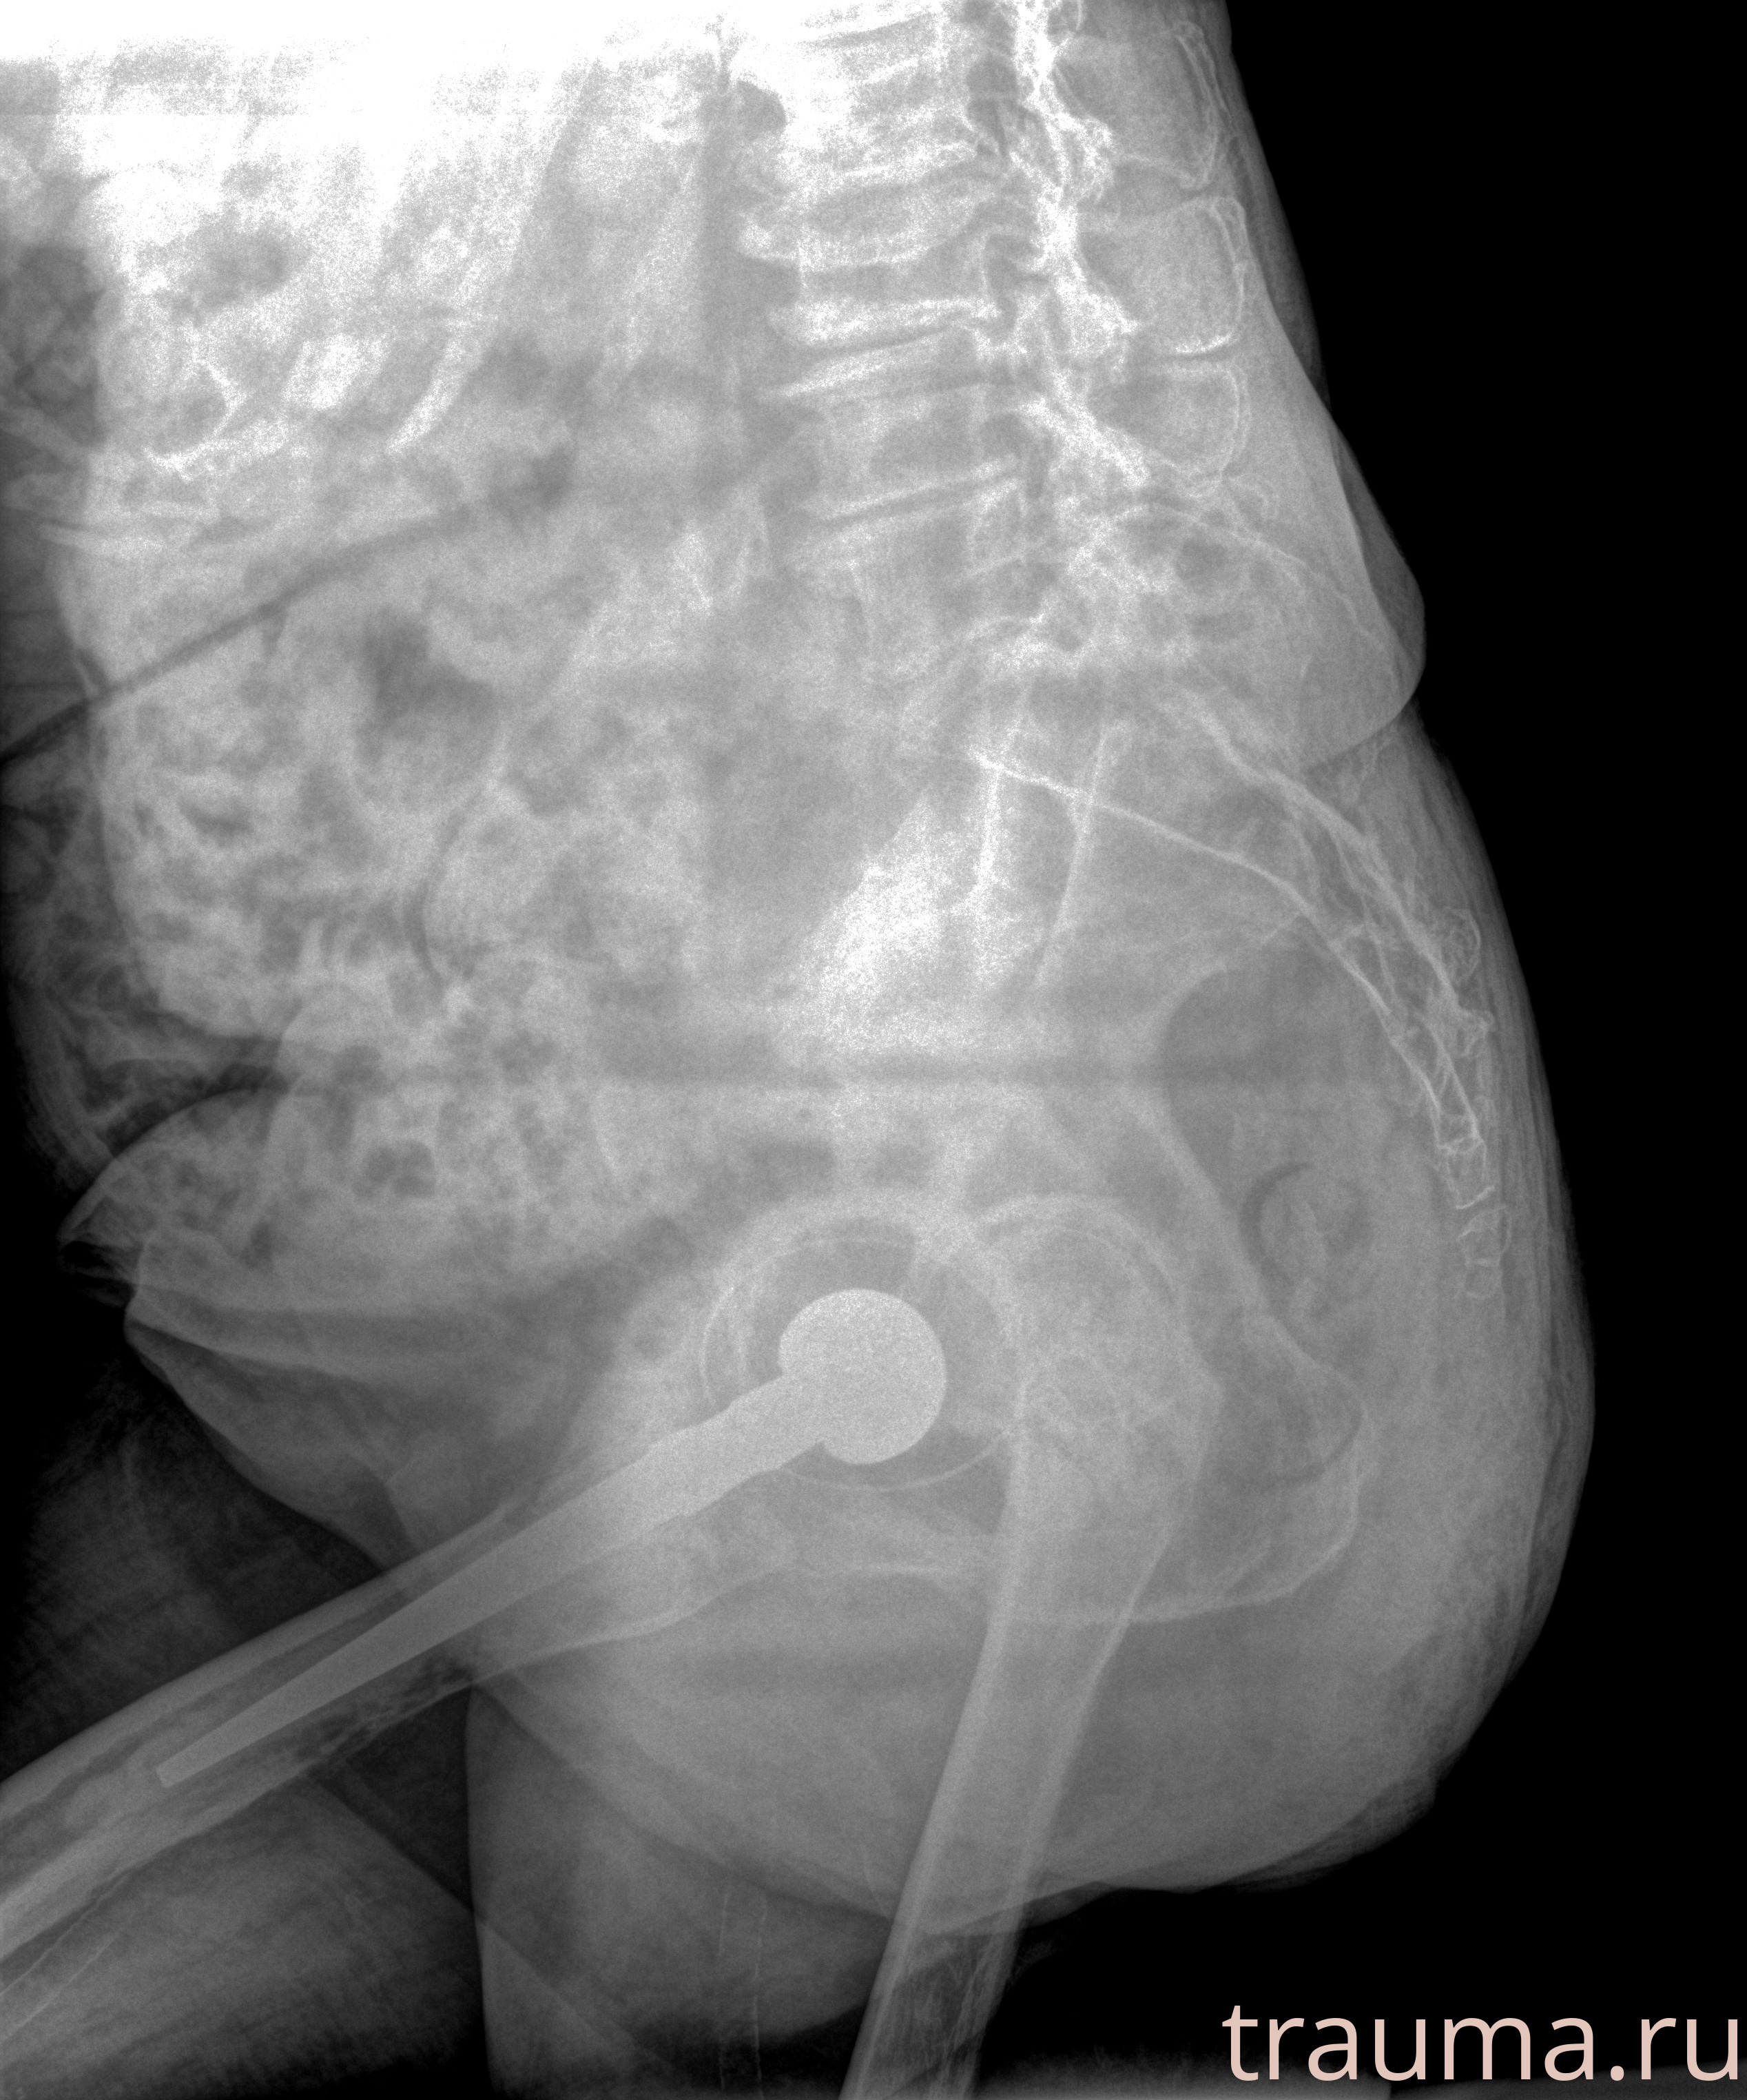

Рентген на дому: по вашему адресу приезжает врач-рентгенолог, травматолог-ортопед с мобильным рентгеновским аппаратом, проводит диагностику травмы или заболевания, делает необходимые рентгенограммы, дает рекомендации по дальнейшему лечению. Получить качественные снимки в домашних условиях возможно благодаря уникальной методике, разработанной МосРентген Центром для института  Склифосовского

при переломе шейки бедра и пневмонии от компании МосРентген Центр - партнера Института имени Склифосовского